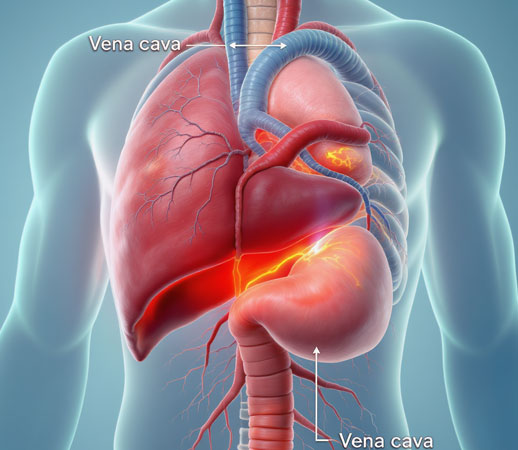

Negligencia Médica